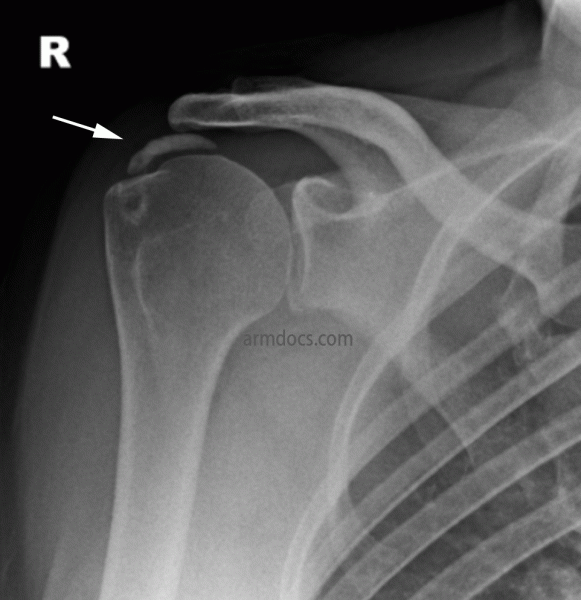

The condition is diagnosed from the history of a painful shoulder, which has developed gradually over time. In the early stages, pain is often aching in nature, usually intermittent and experienced when reaching overhead and often when lying on the shoulder at night. Some patients will experience a sudden onset of excruciating pain, which severely limits their ability to use the arm for even simple daily activities. Examination shows pain with certain movements of the shoulder and on special rotator cuff tests. An ultrasound scan may demonstrate the location and size of the calcium deposit in the rotator cuff. An X-ray is essential to look at the size, location and type of the calcium deposit. MRI scans are generally unnecessary but may sometimes be useful when pain is of acute onset.